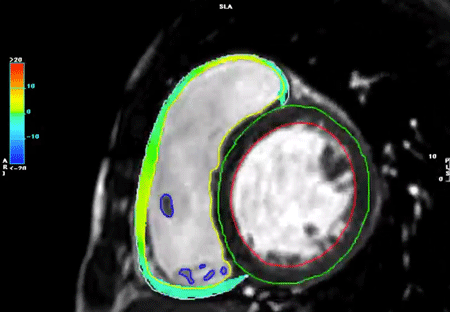

(1)strain(Figs. 11–13, Movies 2–5)

EFよりも心室の収縮能を鋭敏に反映するとされているstrainをCMRで計測可能である.左室だけでなく右室のstrainも計測可能で,最近は心房strainについての報告も出てきている.臨床的な意義についても報告が出てきており,その重要性が注目されている19).またdyssynchronyの検出にstrainを応用する試みも報告されている20)

Fig. 11 Left ventricular (LV) and right ventricular (RV) chamber quantification. For LV chamber quantification, the endocardial (red) and epicardial (green) contours are delineated in a stack of short axis slices and a 4 chamber long-axis. Counters should be marked in the round.

Pediatric Cardiology and Cardiac Surgery 40(4): 260-271 (2024)

Fig. 12 The results of strain analysis. Top: Peak radial, circumferential, and longitudinal strains are shown in AHA 16 segments. Bottom: Each circumferential strains of basal, mid, and apical segment.

Fig. 13 Left ventricular radial strains in 3D view

strainは元来エコーで発展した指標で,CMRでstrainを計測するには,以前は心筋組織にtagを付けて撮影するtaggingという撮影を追加で行う必要があり,手間や時間がかかった.しかし,(撮影機器と)解析アプリケーションの発展に伴い,ルーチンで撮影するシネMRI画像から,feature trackingという方法を用いて後方視的にstrainが計測できるようになった21).feature tracking法はMRIの磁場などとは関係ない,ピュアな画像処理技術に基づいている.不規則性も含めたその画像上の心筋の特徴をとらえることで,細かく分けた心筋1箇所1箇所が心収縮期の中でどのように移動(収縮・拡張)するかを追跡することが可能になったのである.移動速度を計測することでstrainが算出される.feature tracking法という技術革新により,前方視的な研究だけでなく,過去に撮影した症例のシネMRIからstrainを振り返って解析できるようになることも特徴である.時間分解能(1心拍をエコーは60フレーム以上程度,CMRは20~30フレーム程度で撮影)や空間分解能(画像のslice厚)においてCMRはエコーに劣るが,これまで臨床的な意義がはっきりしていなかったstrainの様々なエビデンスがfeature tracking法により集まってきており,今後のさらなる発展が期待される.なお,解像度が悪く,追加撮影も要するtagging撮影は行われなくなった.

strainの解析結果・方法

左室全体としての心筋ストレインをglobal strainといい,それぞれの方向でglobal circumferential strain(GCS),global radial strain(GRS),global longitudinal strain(GLS)と呼ばれる.四空長軸像や左室二腔像,短軸像などの断面像を用いて以下の方法に則って心室strainの解析を行うと,GCS,GRS,GLSがそれぞれ算出される.また,これらの断面を複数組み合わせて同時に解析を行うことで3Dでのstrain解析を行うことが可能となり,AHA 16 segment modelでの結果表示や,心室3Dモデルにカラーを載せて結果を表示することも可能となる.一例として,解析アプリケーション“CVI42”(Circle Cardiovascular Imaging, Calgary, Canada)を用いた解析結果を示す(Figs. 12, 13, Movies 2–5).

一心周期内の任意の一時相で心内膜・心外膜をトレースするだけで,あとはアプリケーションが自動的に心筋の収縮・拡張を心周期全体で追跡し,strainが算出される.

この解析に際してのコツは2つあり,トレースの仕方と解析結果の確認である.

まず,心内膜・心外膜のトレース線は駆出率を算出した際のトレース線をそのまま用いることも可能である.しかし,乳頭筋や右室の索状組織などを心筋に含んだトレース線のままでは,心内膜線が複雑な凹凸を示すため,うまく心筋の収縮を追跡できないことが多い.このため,strainの計測をする際には心内膜のトレース線を,乳頭筋や右室の索状組織などを含ない凹凸のないシンプルな曲線(心腔容積計測では推奨されないトレース線)として描くことがコツである(Fig. 11).

次に,アプリケーションが心筋の収縮を正確に追跡できているか,全スライス・全時相で確認する必要がある.うまく追跡できていない場合には,心筋の動きをしっかり追跡できるように,最初に設定した任意の一時相におけるトレース線に戻って,少しずつ修正して,正確に追跡できるか確認するという作業を繰り返す必要がある.

単心室系での心筋strain計測は,駆出率などを計測した際と同様に2つの心室を1つの心室として扱って行う19)